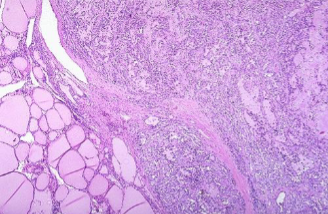

Follicular Thyroid Carcinoma

Capsular invasion in Minimally Invasive FTC

FTC involving most of a lobe